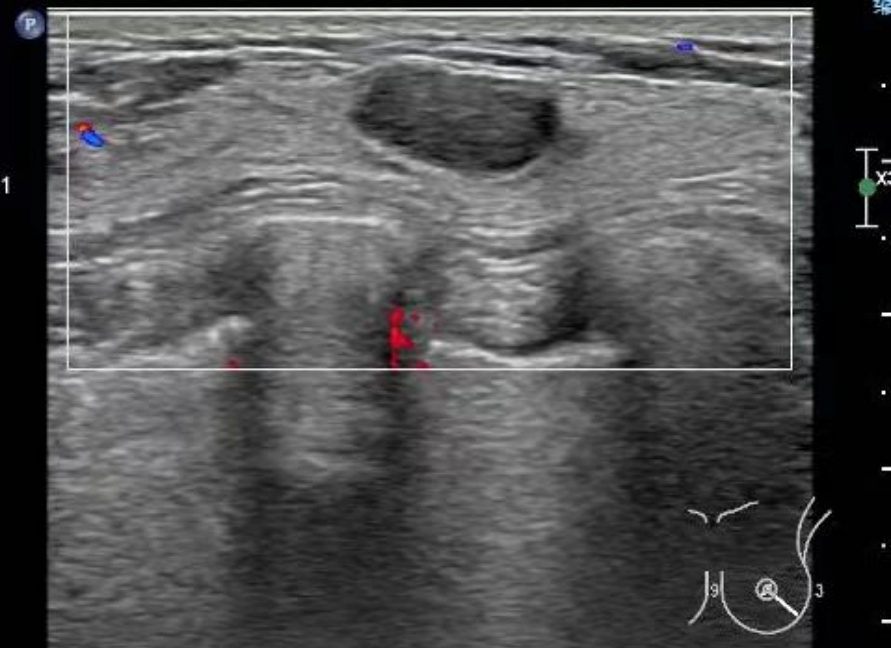

超声提示:右乳低回声结节,边界清,形态规则(考虑纤维腺瘤)